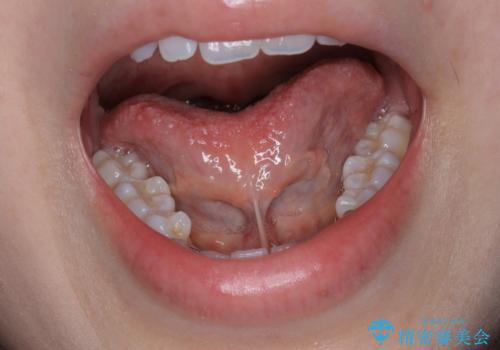

[ 舌小帯の形成 ] 滑舌が悪いと言われる、話しづらい

担当医 大元洋佑

![[ 舌小帯の形成 ] 滑舌が悪いと言われる、話しづらいの症例 治療前](https://seimitsushinbi.jp/wp/wp-content/uploads/2021/07/65efe28f05c8bc8266a054e337d8a987-500x350.jpg?v=1626308574)

![[ 舌小帯の形成 ] 滑舌が悪いと言われる、話しづらいの症例 治療後](https://seimitsushinbi.jp/wp/wp-content/uploads/2021/07/9a0e2d1f2bdecf6d77e84a94c98c2f5e-500x350.jpg?v=1626308612)